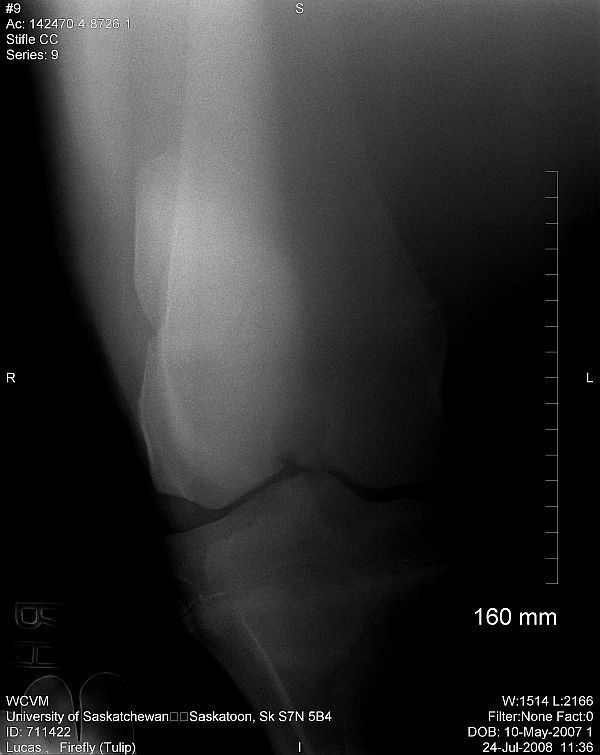

Right stifle

Thanks Dr. O!! I really appreciate your taking a look at this. I do have Dr. Rantanen's report which is as follows:

Interpretation:

The most proximal portion of the right medial tibial spine was separated by an irregular fracture line. The fragment was still close to its anatomic position.

There was no soft tissue swelling or secondary joint disease present at this time.

Comment:

With the absence of clinical signs of lameness, normal flexion and no soft tissue swelling at this time, this fracture most likely occurred at a young age. It may be an incidental finding in this horse. Success in training would confirm that this fracture most likely occurred at a young age and may be tolerated without surgical intervention.